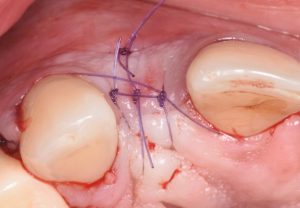

The procedure is presented step by step, including flap design and management, defect assessment, membrane selection and stabilization, flap advancement, and suturing techniques. Emphasis is placed on achieving tension-free closure and maintaining hard and soft tissue contours critical for esthetic success.

- Membrane stabilization techniques for GBR

- Flap advancement strategies to achieve tension-free closure

- Suturing techniques to protect the regenerative site